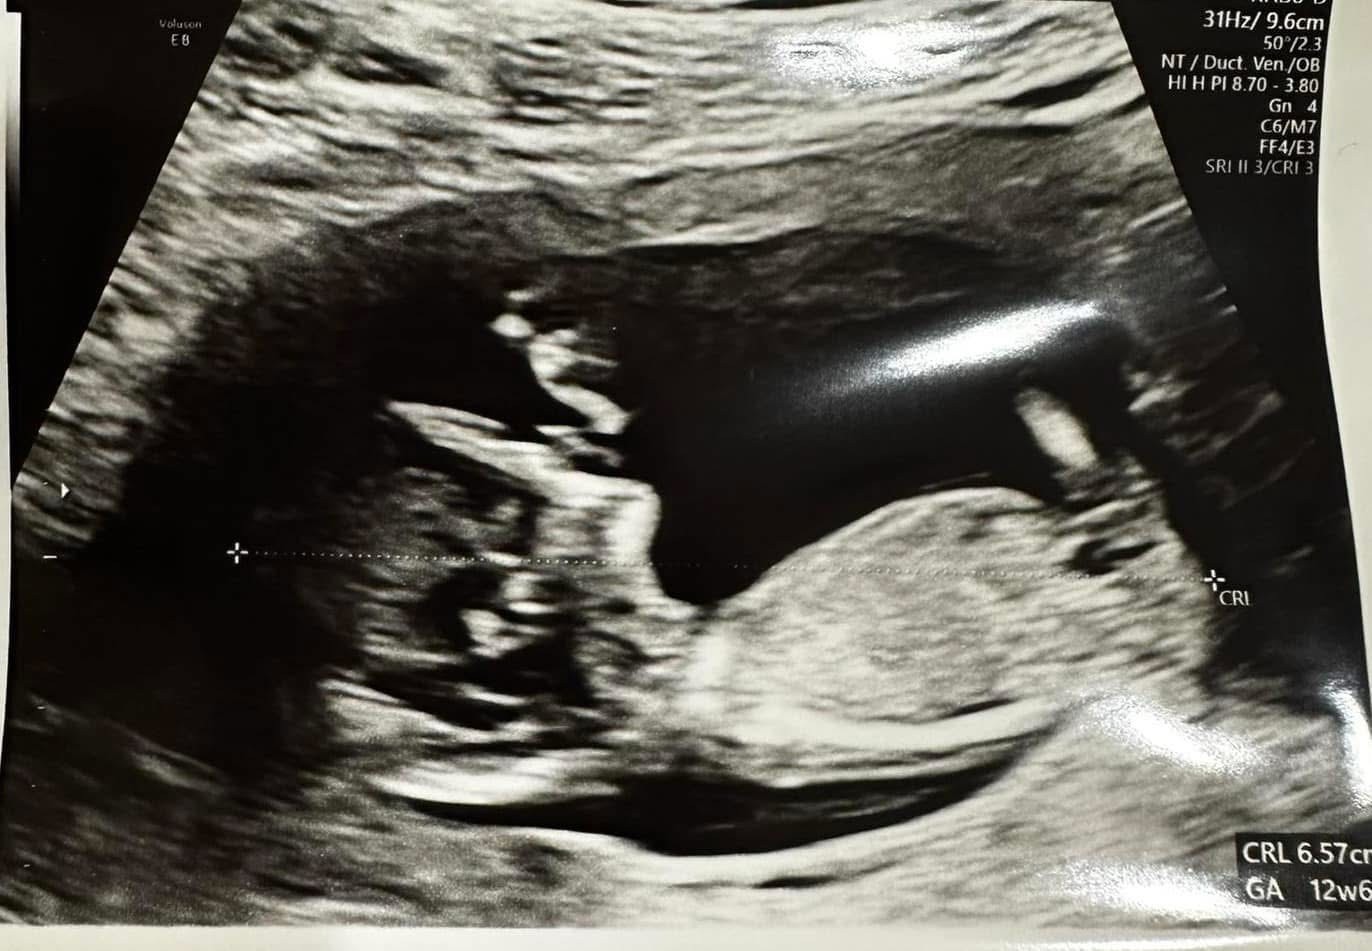

Moje zdjęcie z 12+5, lekarz był pewny że chłopiec i się potwierdziło 🙂

• A14A46D0-2E57-41CF-8C4F-FE28D4175366.jpeg

A14A46D0-2E57-41CF-8C4F-FE28D4175366.jpeg

11,4 KB · Wyświetleń: 111